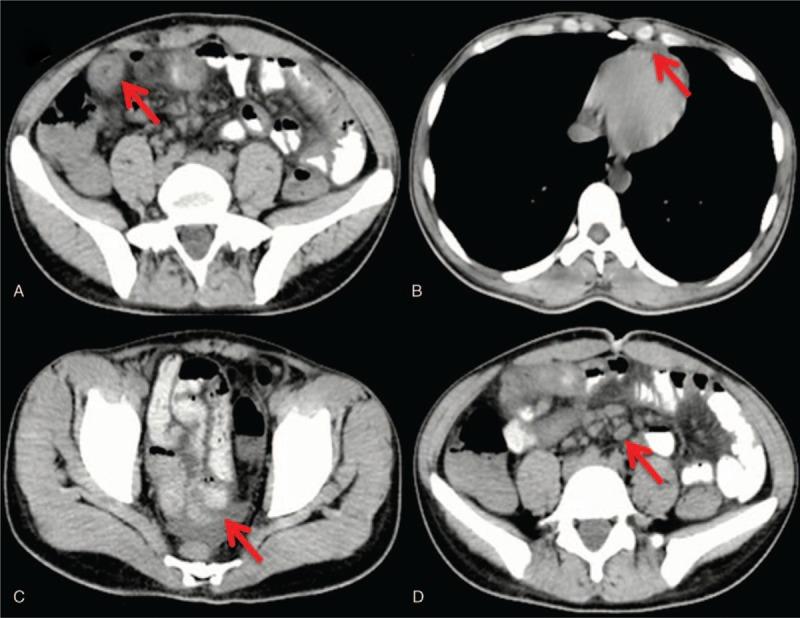

A good response to glucocorticoid for Henoch-Schönlein purpura with abdominal pain and gastrointestinal bleeding in an adult: A CARE case report.

Henoch-Schönlein purpura (HSP) is a small-vessel vasculitis that has been extensively studied in children, but little is known about its natural history in adults. There is no consensus regarding the treatment of glucocorticosteroids use for HSP. The efficacy of glucocorticoid for preventing from severe complications or relapse is also controversial in HSP.

PATIENT CONCERNS

A 21-year-old male was admitted to the hospital due to abdominal pain for more than 20 days, hematochezia for more than 10 days, and rash for 2 days.

The diagnosis of HSP is based on the European League against Rheumatism and the Paediatric Rheumatology European Society in 2006.

The patient received glucocorticosteroids treatment for 17 days at the time of first hospitalization.

The abdominal pain and hematochezia completely disappeared on the 6th day after the use of glucocorticosteroids, and purpura completely disappeared on the 8th day.

Our patient has a good response to glucocorticoid. Glucocorticosteroids may be effective for the treatment of HSP.